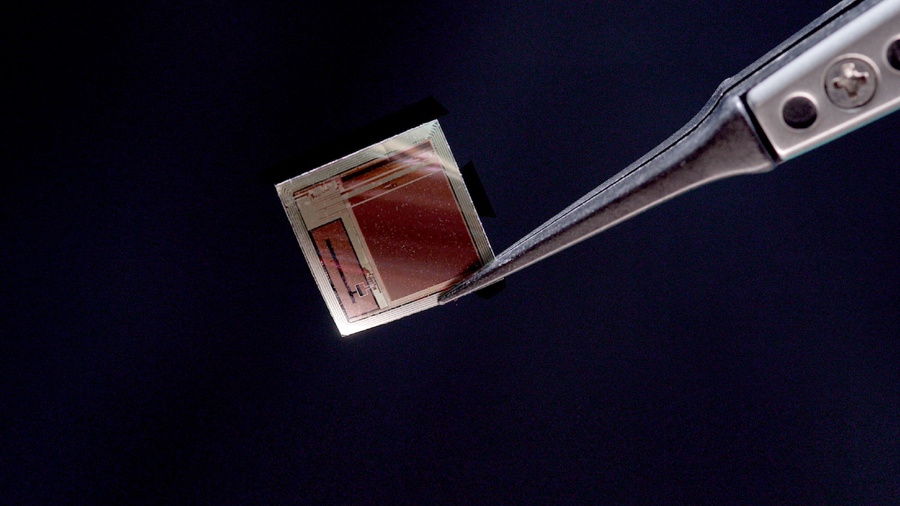

“Nuestro implante es un único chip de circuito integrado tan fino que puede deslizarse en el espacio entre el cerebro y el cráneo, apoyándose en el cerebro como un trozo de papel de seda húmedo”, detalla.

BISC es distinta: todo el implante, que ocupa menos de una milésima parte del tamaño de un dispositivo convencional, es un único chip de circuito integrado de semiconductores complementarios de óxido metálico (CMOS) con un grosor de solo 50 micrómetros, como un cabello humano.

Con un volumen total de aproximadamente 3 mm³, el chip flexible se adapta a la superficie del cerebro pero integra 65.536 electrodos, 1.024 canales de registro simultáneo y 16.384 canales de estimulación.

“Los implantes pueden insertarse a través de una incisión mínimamente invasiva en el cráneo y deslizarse directamente sobre la superficie del cerebro en el espacio subdural. Su forma delgada como el papel y la ausencia de electrodos que penetren en el cerebro o cables que unan el implante al cráneo minimizan la reactividad de los tejidos y la degradación de la señal con el tiempo”, comenta Youngerman.